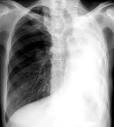

Atelectasis is defined as diminished volume affecting all or part of a lung. Note that the term atelectasis is typically used when there is partial. It may include a lung subsegment or the entire lung and is almost always a secondary. Collapsed Lung (Atelectasis) - Cedars-Sinai Learn more about collapsed lung (atelectasis including symptoms, prevention, causes and risk factors, diagnosis and treatment). Atelectasis - , the free encyclopedia Atelectasis is the collapse or closure of a lung resulting in reduced or absent gas exchange.

It may affect part or all of a lung. Org Lung atelectasis refers to collapse or incomplete expansion of pulmonary parenchyma. Atelectasis (at-uh-LEK-tuh-sis) is a condition in which one or more areas of your lungs collapse or don t inflate properly.

Atelectasis refers to collapse of part of the lung. Atelectasis - Mayo Clinic Atelectasis (at-uh-LEK-tuh-sis) a complete or partial collapse of a lung or lobe of a lung develops when the tiny air sacs (alveoli) within the lung become.